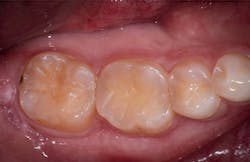

A 27-year-old patient was referred to me due to discomfort associated with dentinal hypersensitivity secondary to erosion on his posterior teeth (figure 1 above: Initial presentation. Note the exposed dentin due to erosion). His former dentist suggested crown lengthening due to inadequate space for full-coverage crowns.

After a thorough evaluation of his clinical presentation, radiographs, and intraoral scan, it was evident that the discomfort was due to exposed dentin. The intraoral scan confirmed there was adequate interocclusal space to restore the eroded tooth structure with a minimally invasive approach (figure 2). All options were reviewed with the patient, and it was mutually agreed upon to address his chief complaint in this manner. Proper isolation is critical for reliable bonding.